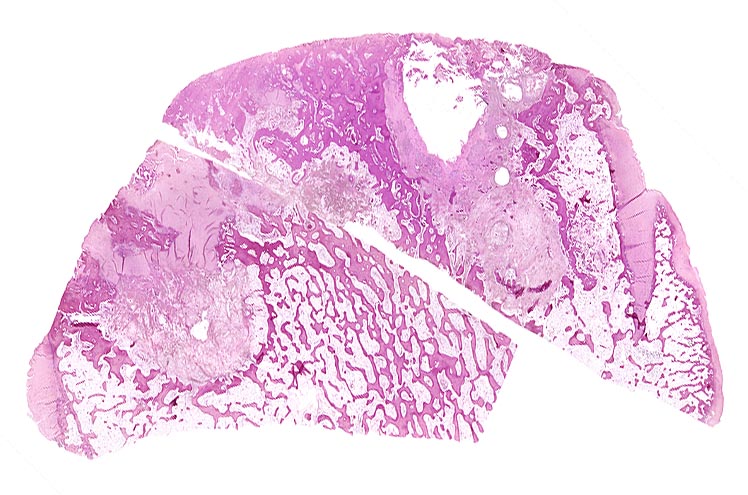

Coxarthrose

Knochen, Femurkopf

Beschreibung

Zusammengehörige topographische Übersichtspräparate eines Schenkelkopfes mit Arthrose, von zwei verschiedenen Paraffinblöcken stammend. Die Präparate passen mit ihren Schnittflächen in etwa zusammen. Im Randbereich erhaltener Gelenkknorpel. Randosteophyt. Geröllzysten.

74-jährige leicht adipöse Patientin mit Anlaufschmerz, belastungsabhängigem Schmerz und zunehmender Versteifung im Hüftgelenk. Im Röntgenbild des Hüftgelenks zeigen sich eine Gelenkspaltverschmälerung, subchondrale Osteolysen, Usuren und randständige Osteophyten.